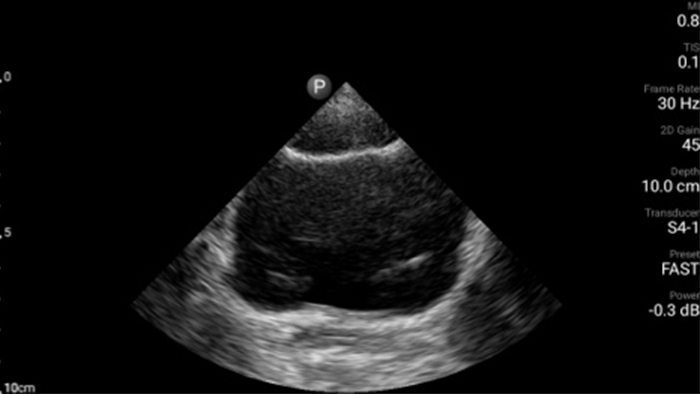

Transductor de disposición en fase de banda ancha Lumify S4-1

• Rango extendido de frecuencias de operación de 4 a 1 MHz • 2D, Doppler a color, Modalidad M, XRES avanzado e imágenes armónicas multivariables • Imagenología de alta resolución para aplicaciones abdominales y cardíacas: optimizaciones de preajustes de imágenes cardíacas, gineco-obstétricas, pulmonares, abdominales y FAST.